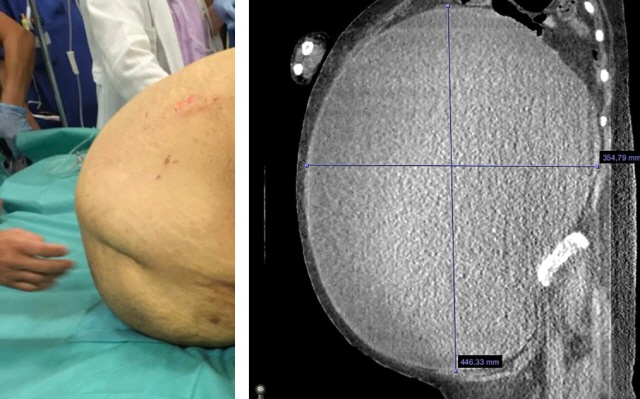

산부인과 초음파검사 결과, 여성의 복강 내에는 거대 난소낭종이 가득 들어찬 것으로 확인됐다. 난소낭종은 여성호르몬을 만드는 난소에 수액 성분 물혹이 생긴 것으로, 치료하지 않아도 자연 소멸되는 경우가 많지만, 드물게 10cm 이상 커지면서 복부팽만, 통증 등을 유발하기도 한다. 낭종이 터지면 등이나 아랫배에 심한 통증을 느끼고, 메스꺼움, 구토, 발열, 어지러움이 발생할 수도 있다. 사례에 소개된 여성의 경우 난소낭종 크기가 세로 44cm, 가로 35cm에 달했으며, 거대 난소낭종이 장과 후복막을 압박하고 있었다.